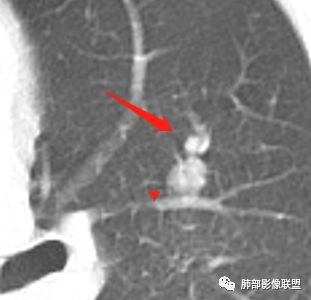

结节与下面的病灶有关系吗?

我们捋一捋

几个结节

下面这一支堵了

前后对比,这些结节其实是没引起支气管远端病变的

南大标注,这几个确实结节没有阻塞支气管,感觉是在血管分叉地方。

@南边 关键是上面这几个结节有的密度度,有的密度低。与下面堵塞支气管的结节样改变是否不是一回事,

如果下面堵塞是恶性,那上面的是不是考虑转移?另外一年结那个疑似结节的地方与现在堵塞的地方好象不一致。

常规腔内病灶引起远端炎症:

我们需要做的:我认为最主要是发现支气管腔内病灶